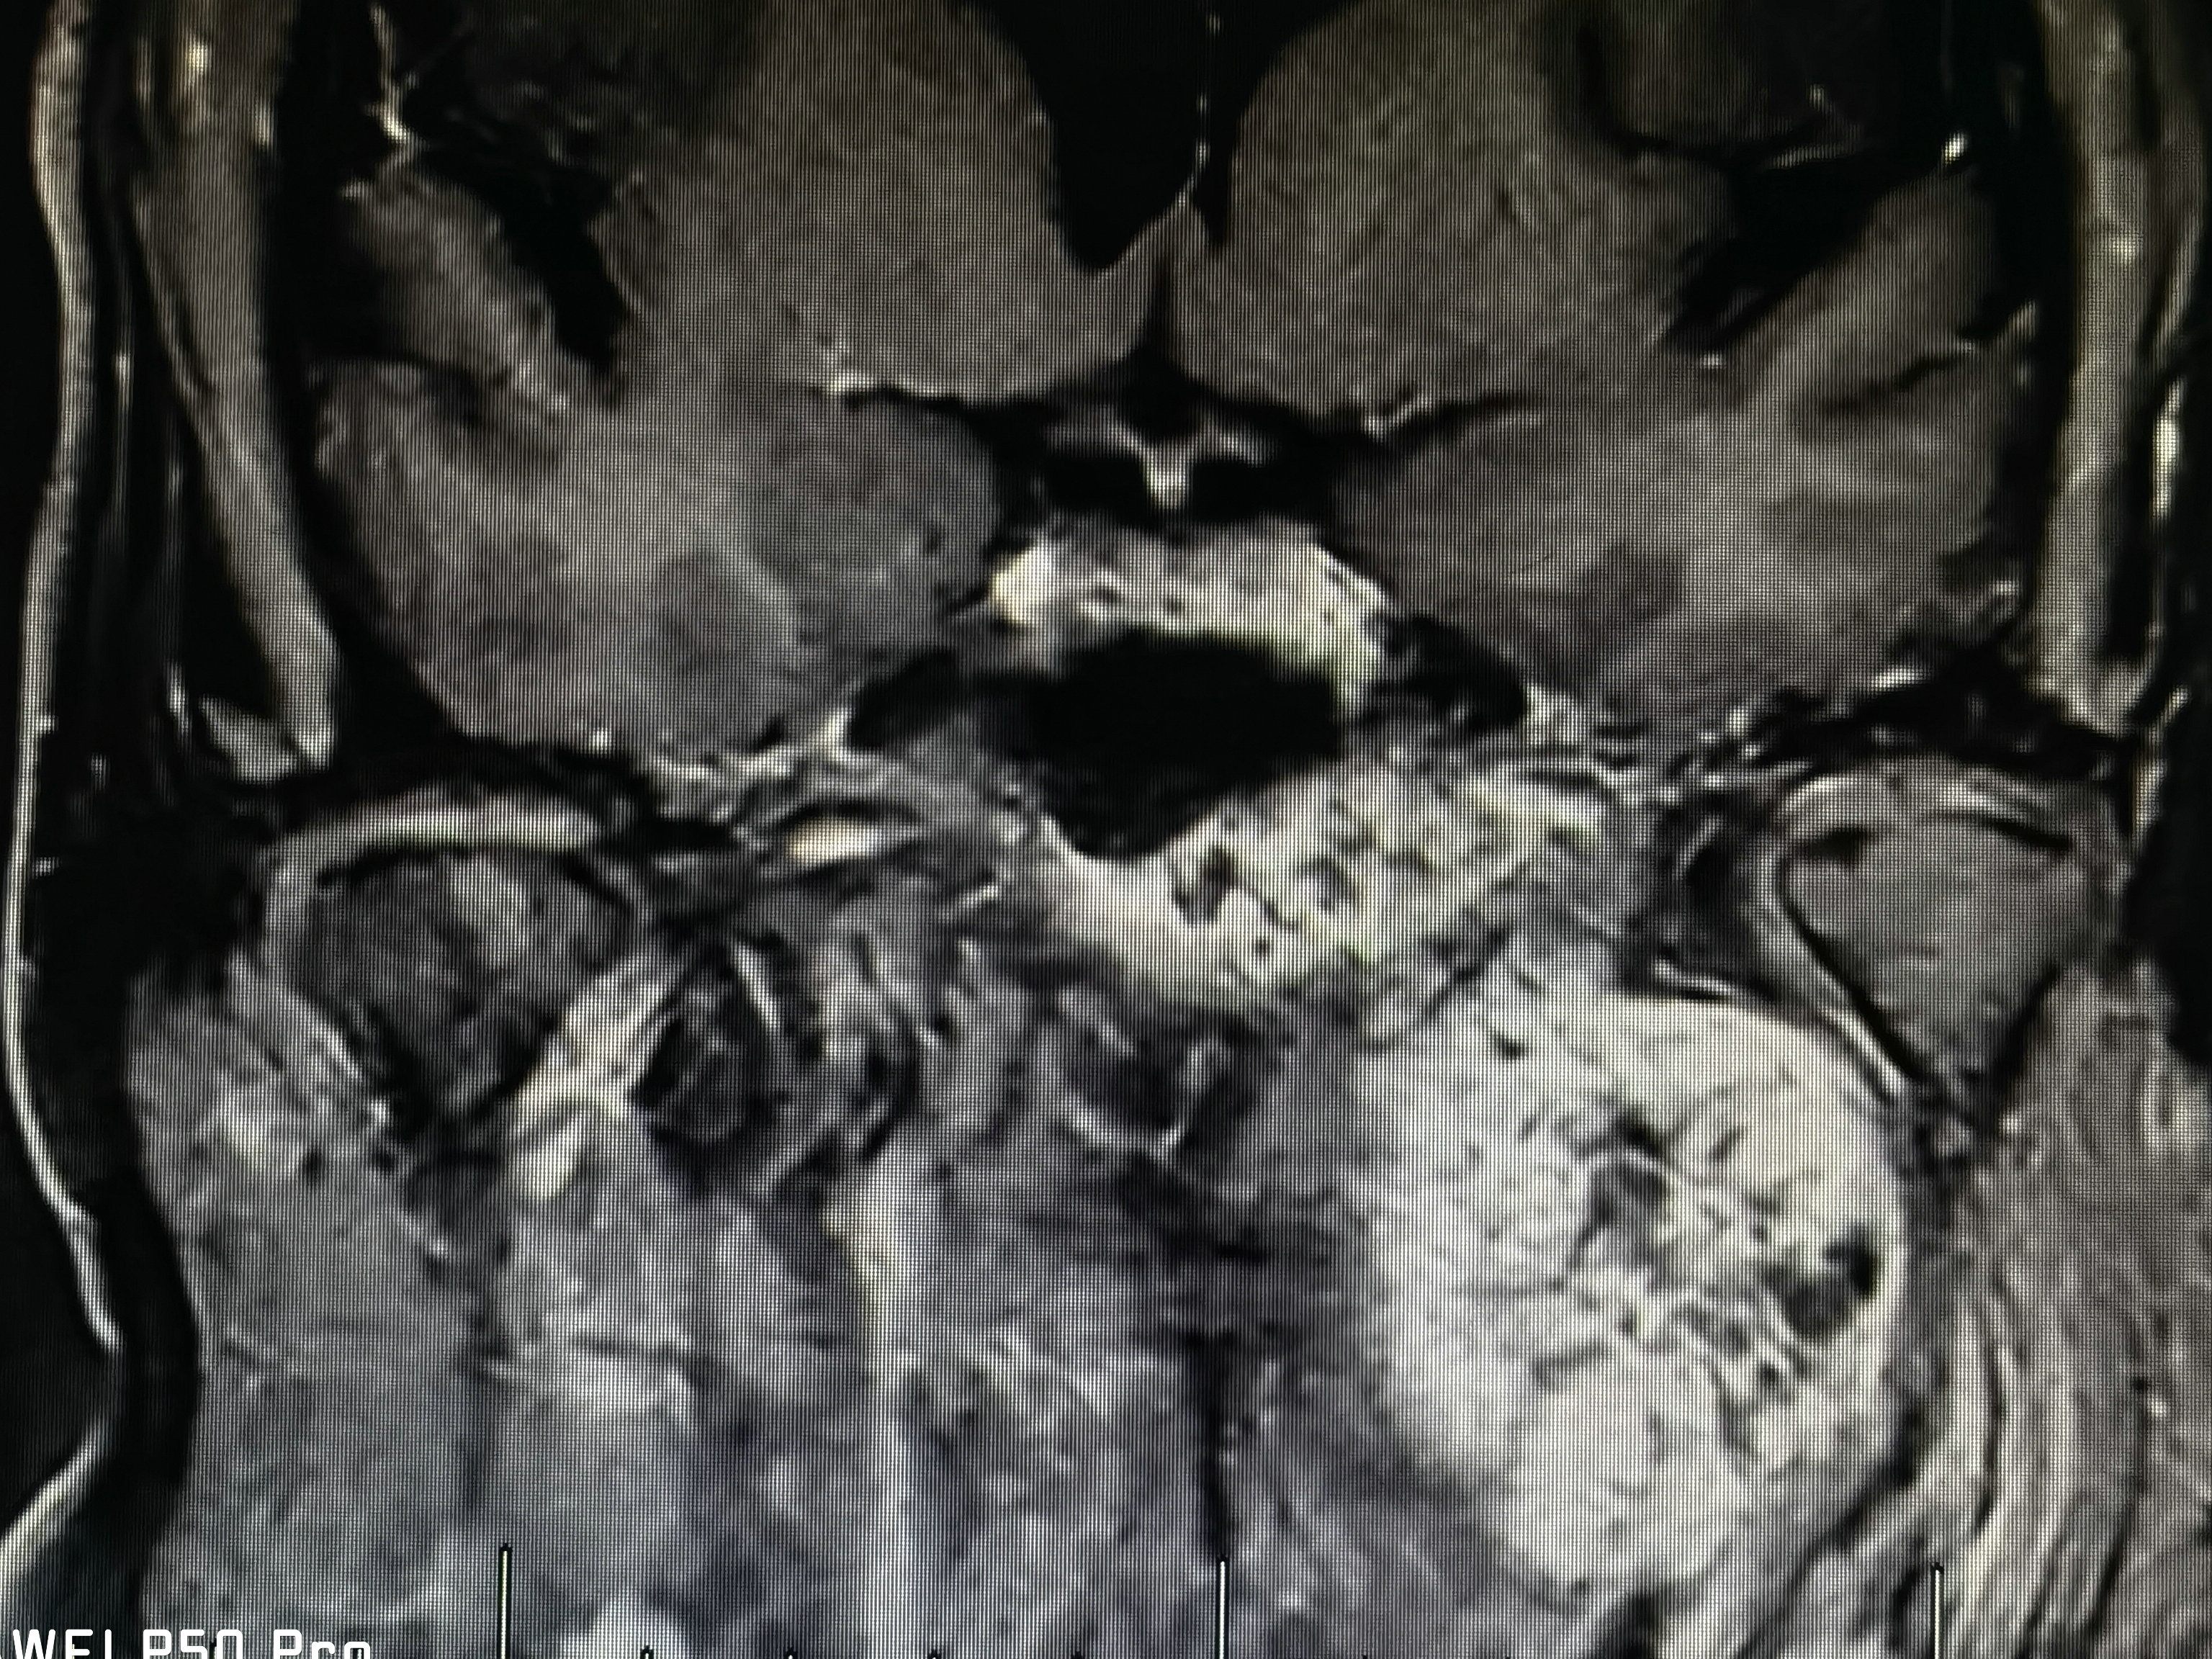

术前磁共振